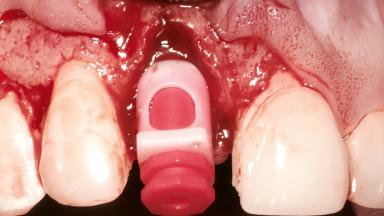

Replacement of a Maxillary Right Central Incisor Using an Early Loading Protocol

Bone Augmentation Horizontal|Simultaneous

Augmentation Materials Autogenous chips|Membrane

Soft Tissue Grafting Simultaneous

Bone Volume Deficient horizontally, allowing simultaneous augumentation